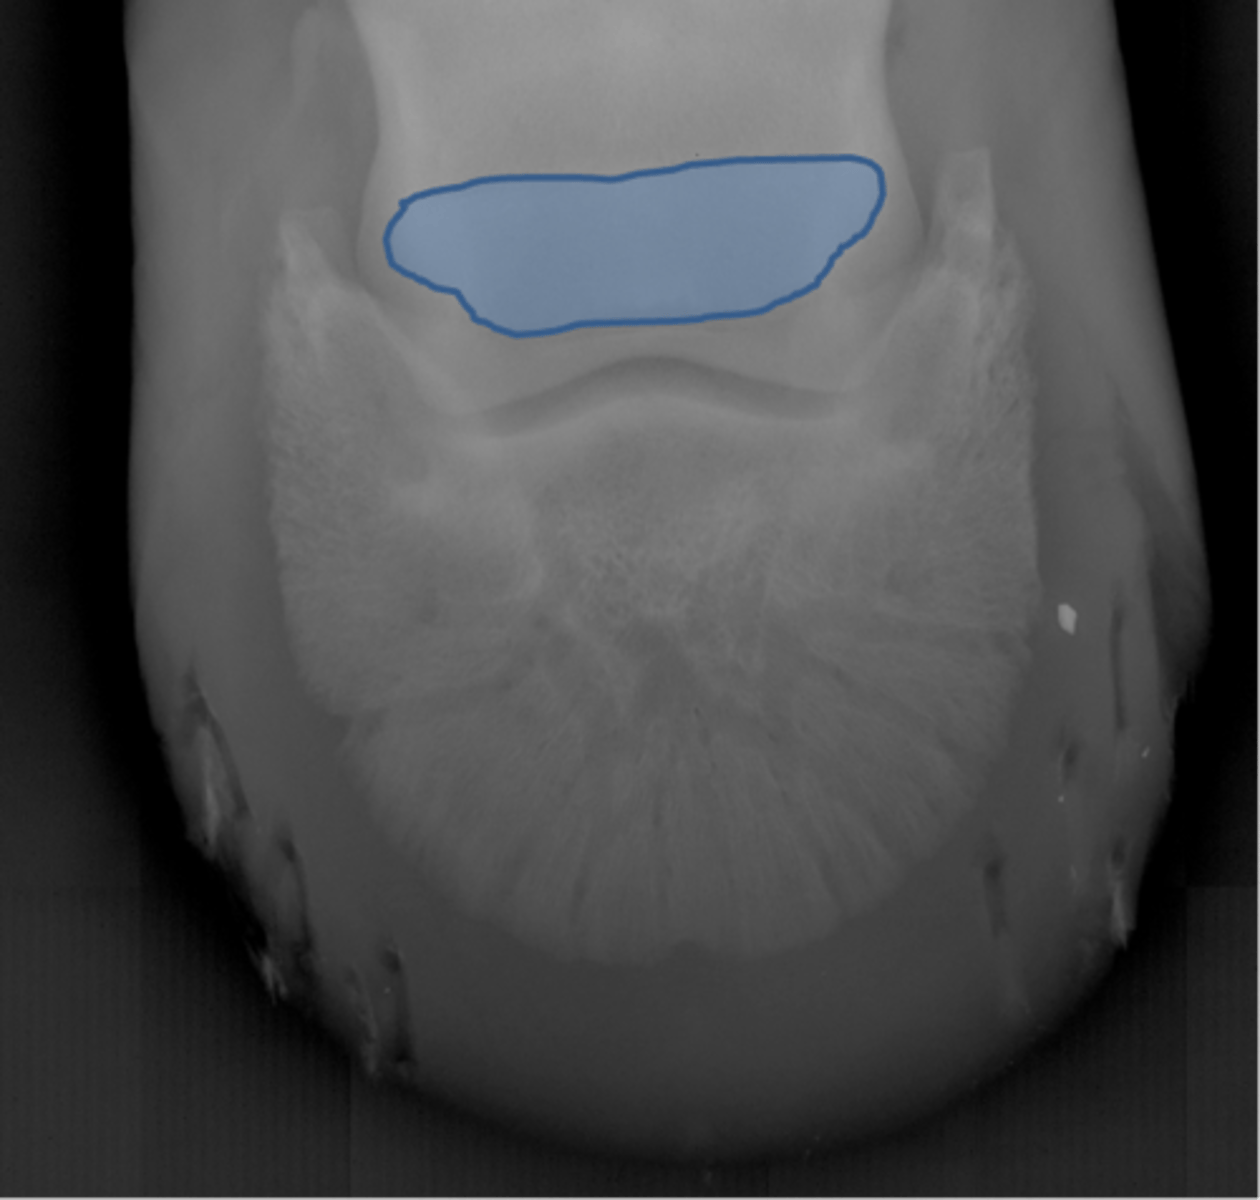

Coffin bone (P3)

Palmar process of P3

Extensor process of P3

Coffin bone

Navicular bone

Crena

Vascular channelsv

Solar canal